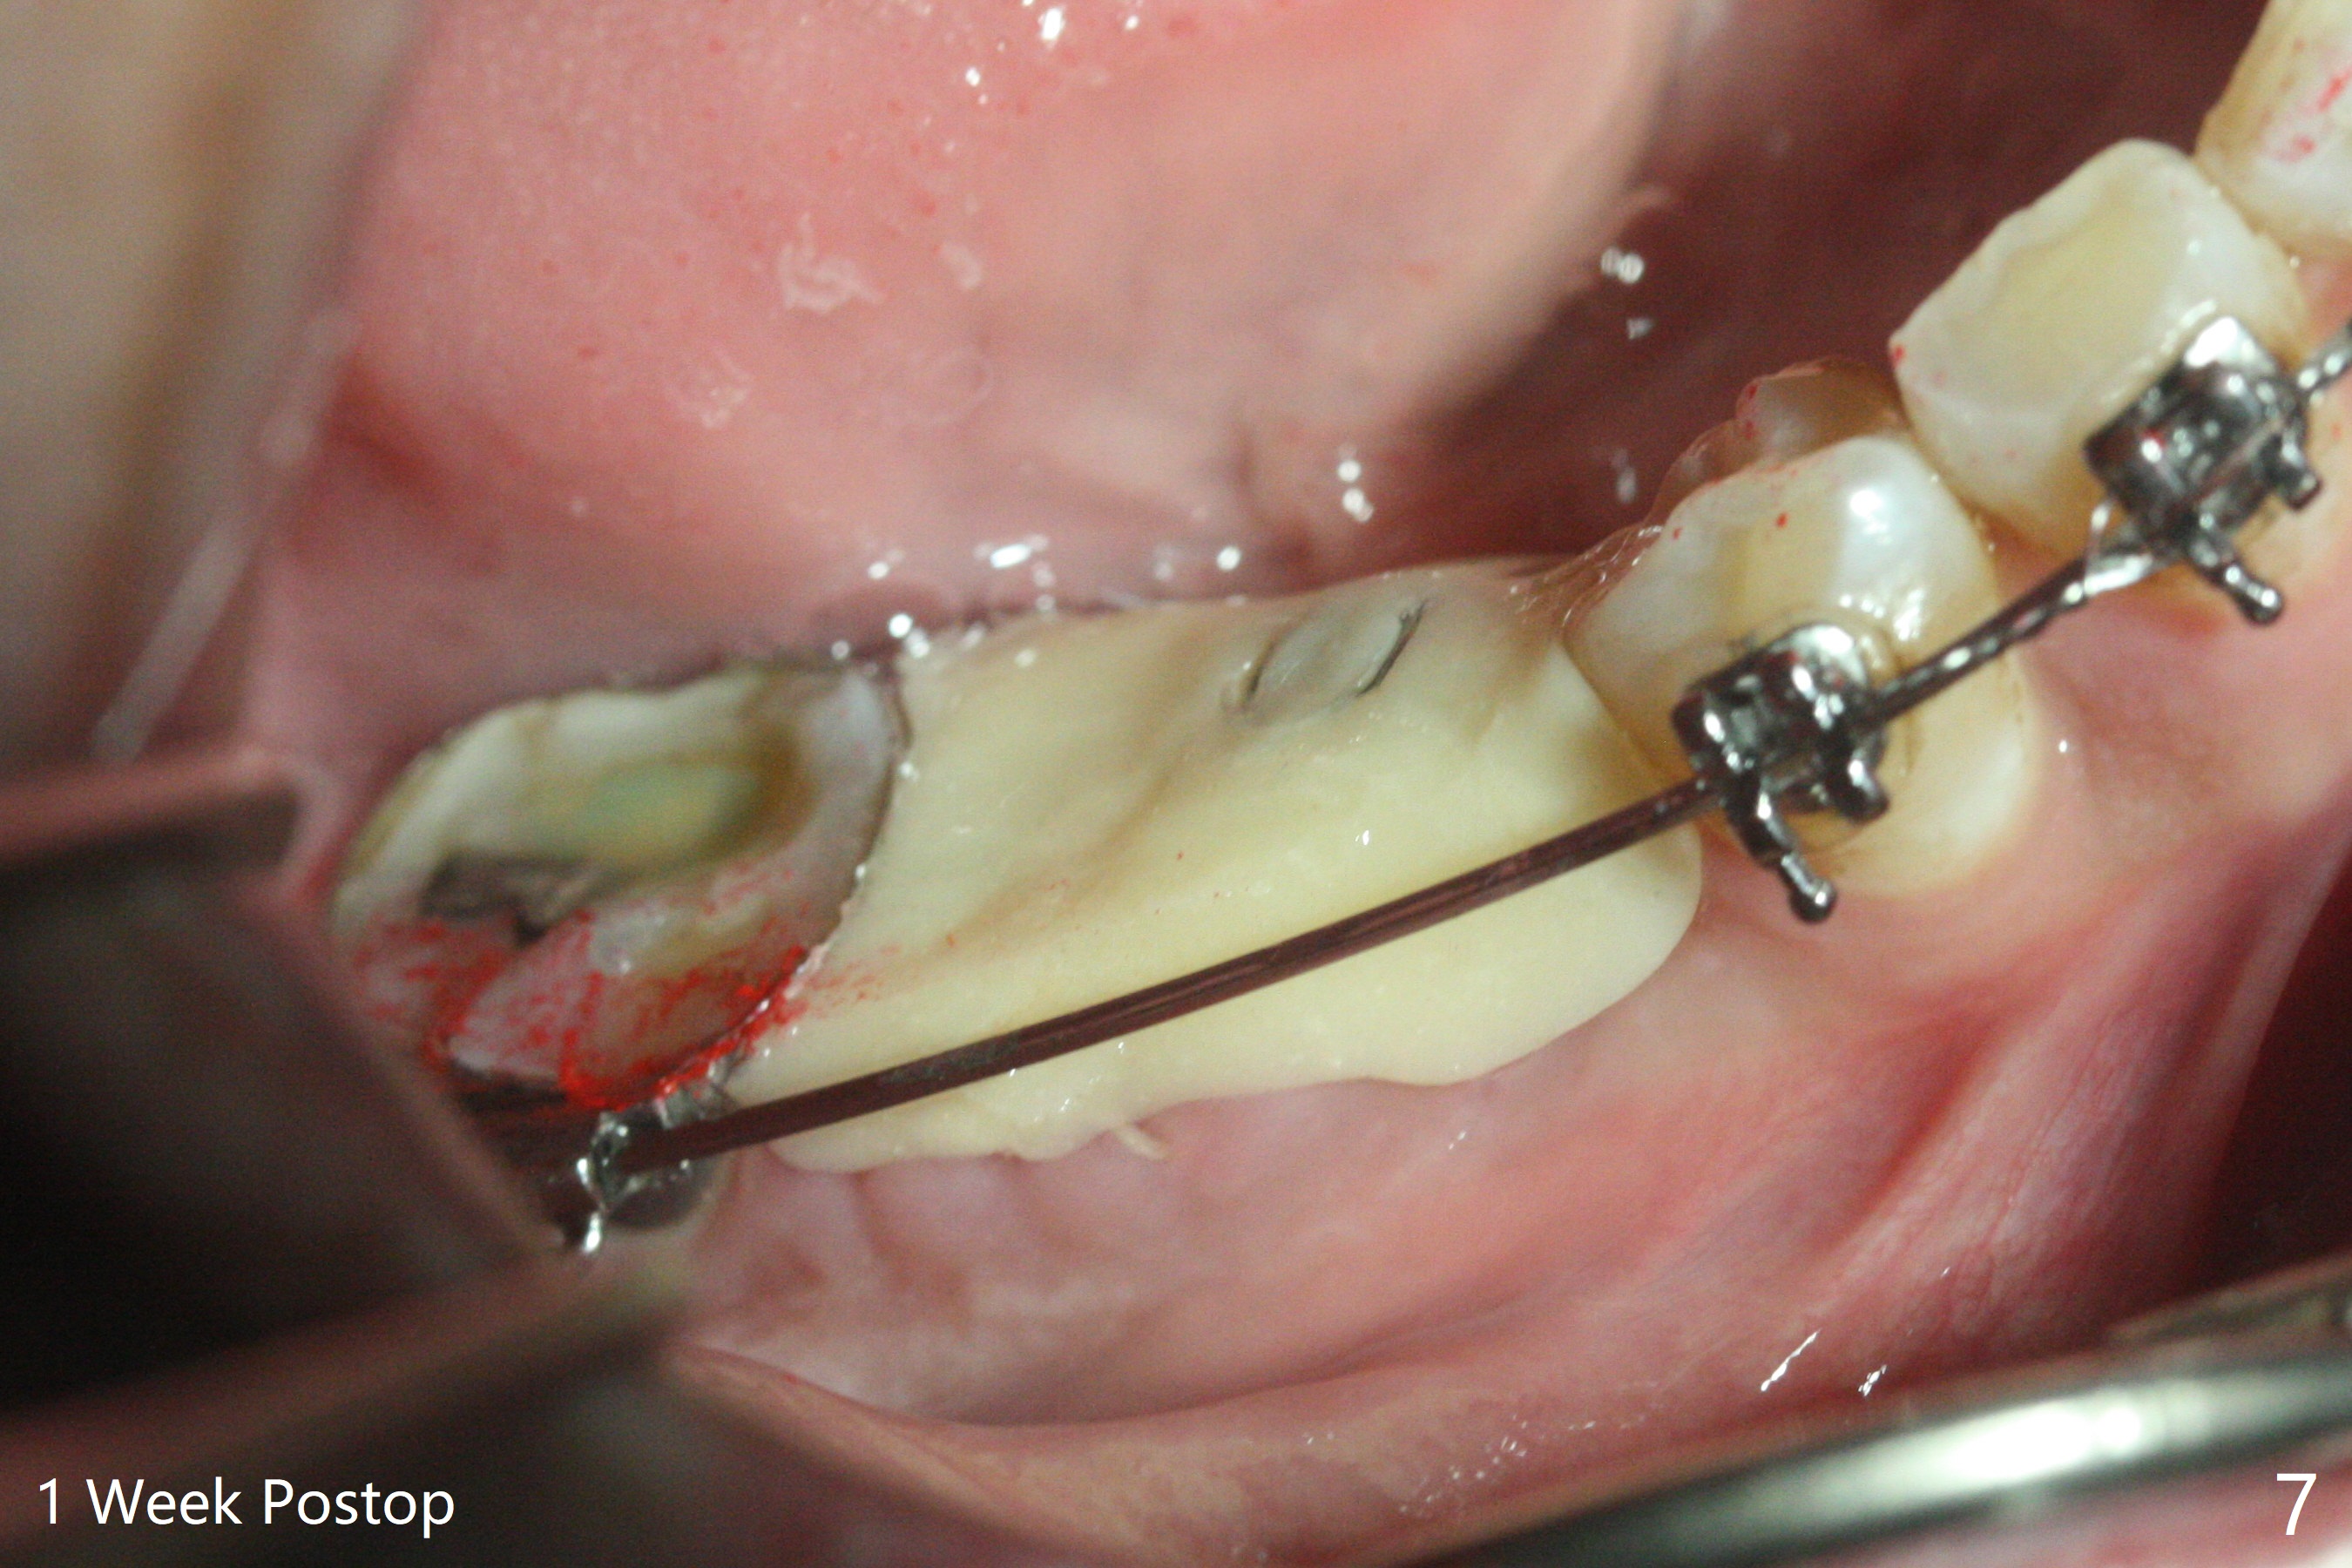

35岁男牙齿矫正后2年5个月右下6远中深龋,拔除后,近中根尖肉芽组织(图零(术前CT冠状切面):*)刮除疼痛,必须阻滞麻醉才能控制疼痛,可能与下牙槽神经分支(图零:红箭头)有关。原先准备在近中牙槽窝近中种植(5x11.5mm),术中发现近中牙槽窝种植好像方便,位置不错,不由自主在那里开始钻洞,由于牙槽窝深,钻洞必须13毫米(图一(接近神经:红虚线)),之后发现钻洞(图二(术前CT3D长轴切面(黑色:近中,远中牙槽窝)):红圆圈)不够理想,使用Lindamann Bur将钻洞往颊侧近中移动(图二:箭头),最终在这方面结果可以(图三,三’,四),虽然接近神经,术后没有神经麻痹。放置粘性骨粉(图四:*),PRF膜,4-0 PGA缝线(图五),最后使用树脂敷料(图六:A)。后牙垂直空间少,术后一周需要降低树脂敷料高度(图七)。术后一个月取出敷料,牙槽窝愈合,植体平台远中稍微暴露(图八),准备一个月后制作临时牙冠。术后两个月植体远中没有暴露,但是基台远中边缘太高了(图九:>),换成6x4毫米愈合基台。下个月换成袖短的修复性基台,安置临时牙冠,牵拉7。舌侧cleats之间放置power chains,颊侧power hooks。其实术后4个月安置临时牙冠和band(图十),牙冠牙合面加高,这样7可以无阻挡移动(图十一:*;16x22 arch wire)。7远中放置power hook行不通,因为末端碰到颊侧前庭牙龈,造成创伤。只好用7颊侧原有牵引勾,在6近中安置一个短的power post (? 图十:箭头),按常规post往下,之间放置12毫米closed spring。如果post往上安置,7牙根牵引可能更有效?近中牵引一个月,第二磨牙前移大约2毫米(图十二:^),稍微近中倾斜,closed spring从12毫米更换到9毫米,舌侧换新的power chains x 4。下一个预约,用sensor 1拍摄根尖片证实第二磨牙近中倾斜,然后在它远中16x22钢丝安放power hook,下缘向颊侧弯曲,避免接触接触粘膜。